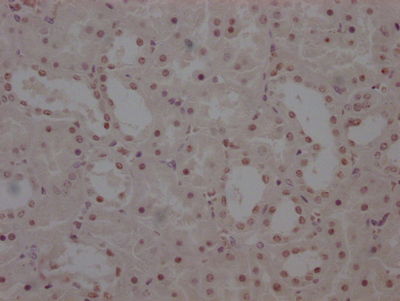

IHC image of CSB-PA892485ESR1HU diluted at 1:50 and staining in paraffin-embedded human endometrial cancer performed on a Leica BondTM system. After dewaxing and hydration, antigen retrieval was mediated by high pressure in a citrate buffer (pH 6.0). Section was blocked with 10% normal goat serum 30min at RT. Then primary antibody (1% BSA) was incubated at 4°C overnight. The primary is detected by a Goat anti-rabbit polymer IgG labeled by HRP and visualized using 0.05% DAB. Secondary antibody only control: uses 1% BSA instead of primary antibody